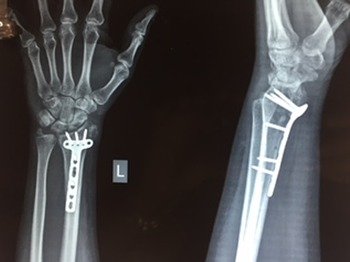

Fractures that have had a delay of more than 3 weeks to seek medical attention from the time of the accident or injury cases which have been mismanaged at the initial stage. Special care is required for neglected fractures.

These surgeries are the most difficult and challenging to treat. Dr Narula uses 3 generation techniques with special implants and Grafts to treat such complicated cases.